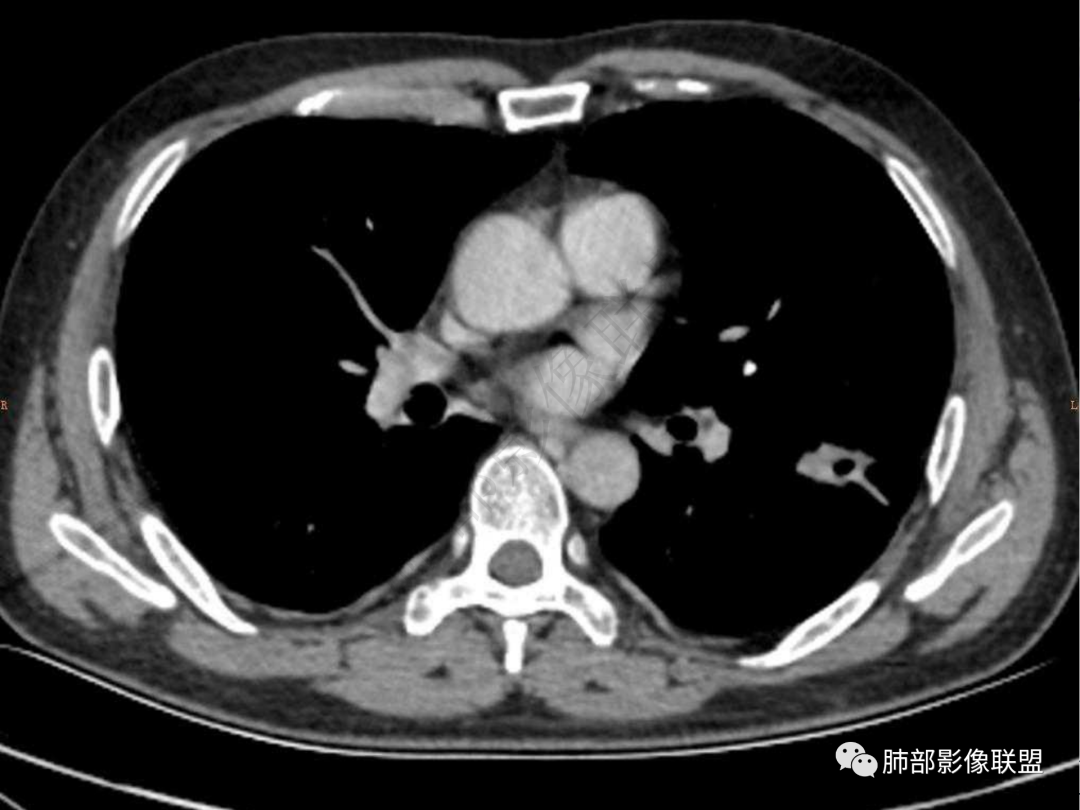

4.实性部分不均匀环形强化并显示一小范围低密度坏死区或空洞。较之肺窗,整体纵隔窗范围较小,提示病灶并不十分密实。抑或为不同时段图像。

5.双肺门及纵隔未见增大淋巴结。未见胸腔积液。